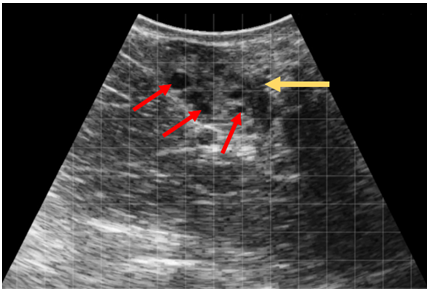

Journal Club – Ultrasonographic diagnosis of femoral fractures in large animals